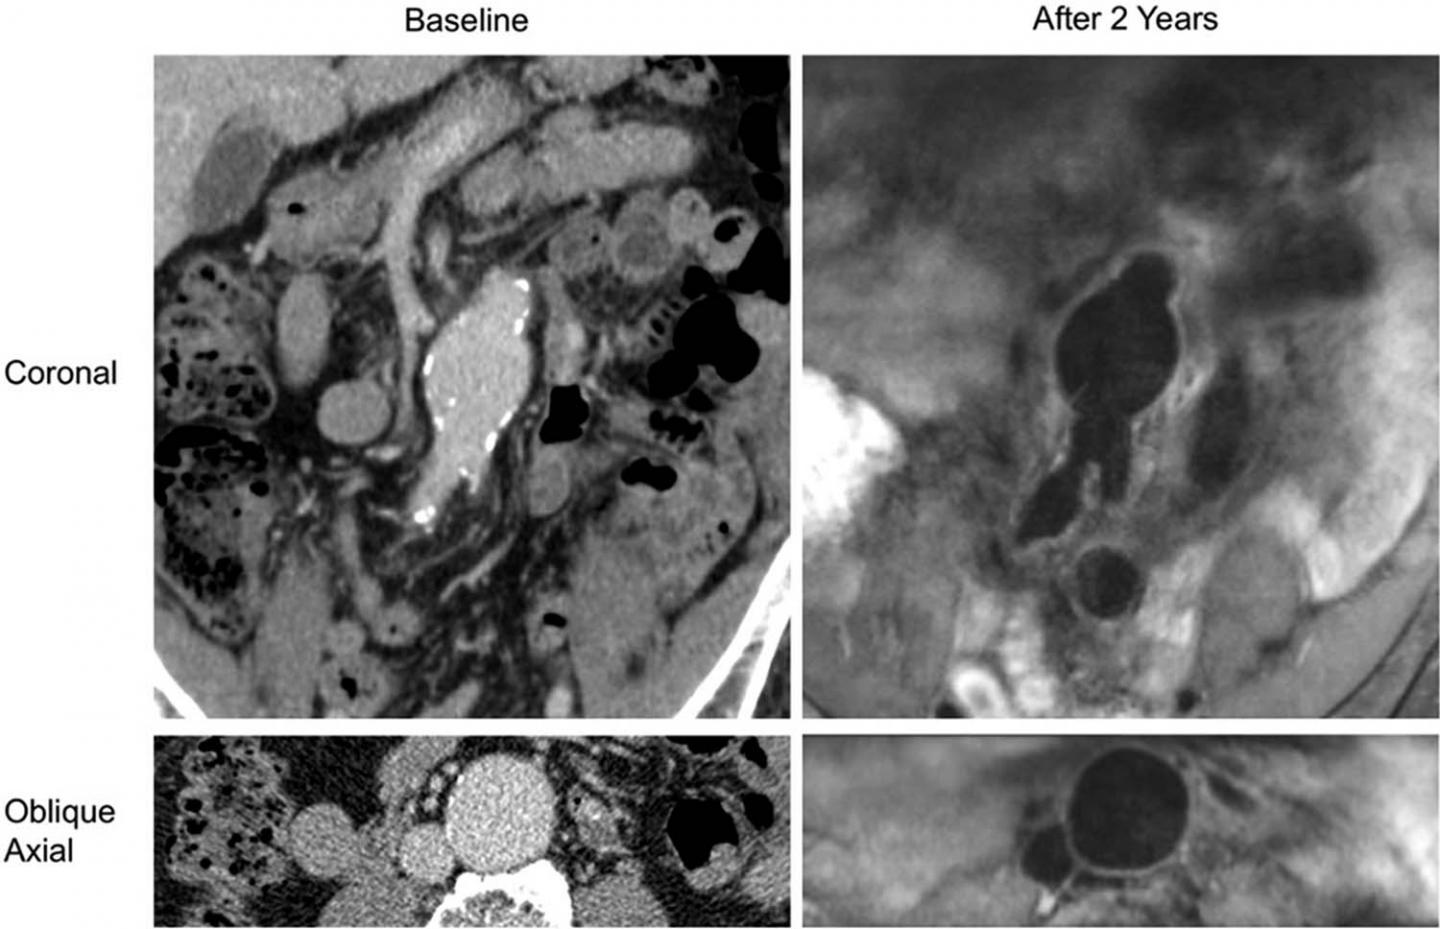

Dr. Zhu and colleagues focused their study on the intraluminal thrombus, a blood clot on the wall of the aorta at the location of the aneurysm. Intraluminal thrombi are present in the majority of aneurysms close to the repair threshold of 5.5 cm, and in a considerable number of smaller aneurysms. Despite their prevalence, the influence of these clots on abdominal aortic aneurysm growth and rupture risk is still not fully understood.

The researchers used high resolution cross-sectional imaging with CT or MRI to assess 225 men with abdominal aortic aneurysm. Follow-up lasted, on average, more than 3 years.

Slightly more than half of patients had an intraluminal thrombus. The aneurysms of those with intraluminal thrombus were larger at baseline and grew by a rate of 2 millimeters (mm) per year, twice as fast as the 1 mm per year growth rate in people without intraluminal thrombus.